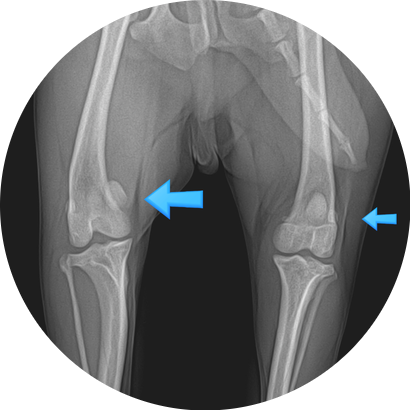

강아지 슬개골 탈구 단계 구분법 / 댕댕이 슬개골 탈구 수술이 필요한 단계는? / 반려견 무릎 수술을 해야 하나요?/ 강아지 슬개골 탈구 전문 동물병원

안녕하세요~ 굿파파 수의사입니다. 약간 흐린 하루네요~^^* 덕분에 선선한 날씨에 기분이 좋답니다. 오늘도...